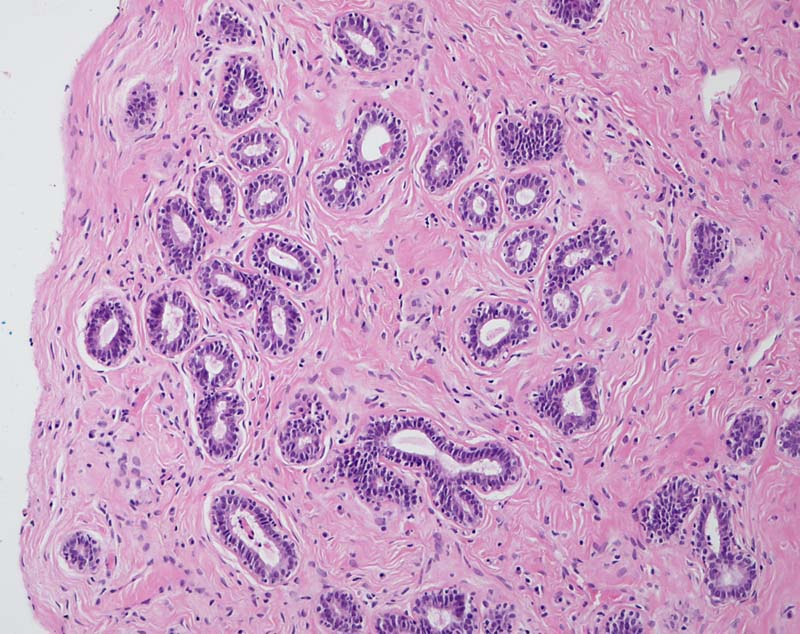

PathoPic ID 8281 - Perikanalikuläres Fibroadenom der Mamma

Perikanalikuläres Fibroadenom der Mamma

benigner Tumor

Mamma

Scharf begrenzter Tumorknoten bestehend aus bindegewebigem Stroma und glanduläre, nicht komprimierte epitheliale Elemente mit runden bis ovalären Lumina (perikanalikuläres Fibroadenom).

V. a. Fibroadenom Mamma links.

Histologie

100

21